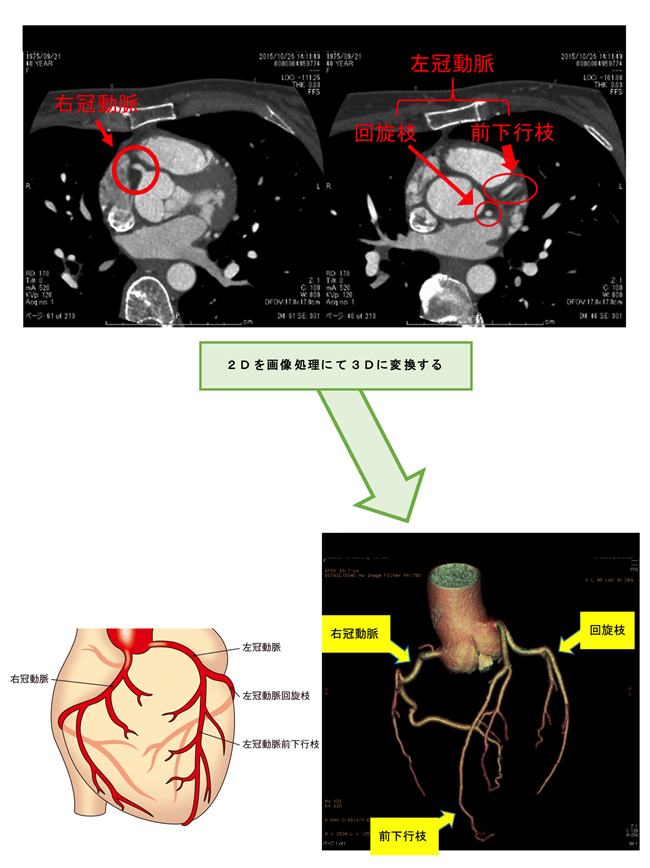

冠動脈CT検査とは

冠動脈CT検査は、心臓を栄養する冠動脈という血管を調べる検査です。カテーテルを使用せず、造影剤を注射することで、今までは心臓カテーテル検査でしか分からなかった冠動脈の形態評価ができます。

冠動脈が細くなり、心臓に十分な酸素がおくれなくなることによっておこる狭心症・心筋梗塞などの虚血性心疾患や、血管の走行異常などを早期に発見することができます。

冠動脈CT検査は心臓カテーテル検査に比べ、患者様への負担が少ない検査法です。検査にかかる時間も短く、低コストで、入院する必要もありません。